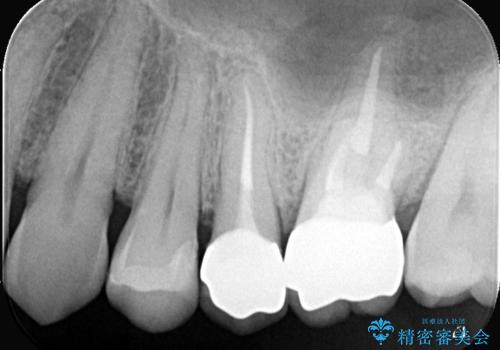

- お口の中にある銀歯を全てなくして、白く健康的な状態にしたい」という主訴でご来院されました。長年使用してきた複数の銀歯は、経年劣化により適合が悪くなっており、一部では内部で二次カリエス(虫歯の再発)も認められました。

患者様と相談の上、全ての金属(メタル)を取り除き、生体親和性が高く審美性に優れた素材へ置き換えるメタルフリー治療の計画を立案。部位や欠損の大きさに合わせ、セラミックインレーおよびセラミッククラウンを用いて、お口全体の調和を整えることとしました。

銀歯の除去と精密な再治療: 古い銀歯を一つひとつ丁寧に取り外し、内部の虫歯を徹底的に除去。神経を保護するための処置を行った上で、適合性を極限まで高めるために精密な型取りを行いました。

オールセラミックによる修復: 天然歯のような光の透過性と硬さを持つオールセラミックを使用しました。奥歯であっても、患者様固有の歯の色調や咬み合わせの溝を忠実に再現した修復物を装着。金属を一切使用しないことで、金属アレルギーのリスクを排除し、歯肉の色が黒ずむ心配もなくなりました。

【治療の結果】 全ての銀歯が白くなったことで、お口の中がパッと明るくなりました。見た目の美しさだけでなく、表面が滑らかなセラミックはプラークが付着しにくいため、将来的な虫歯や歯周病の予防効果も高まった健康的な口腔環境が実現しました。